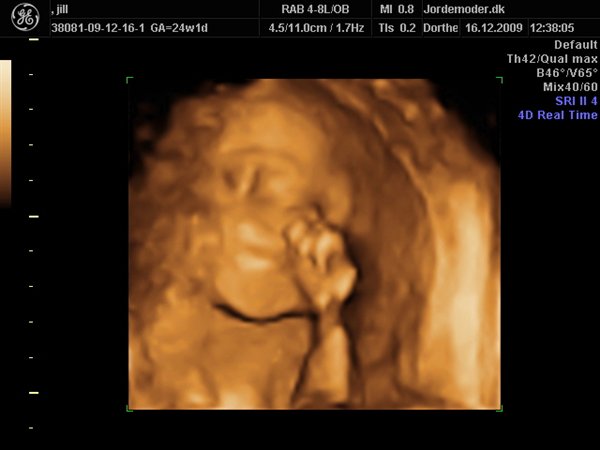

Da jeg snakkede med hende i dag sagde hun at fra uge 27 til og med uge 31 var det bedste tidspunkt at få det gjort....

Vi skal give 1400 kr for 45 minutters total gennem scanning, hvor hun fortæller, undersøger babyen fra top til tå, laver vægtskøn også får vi billeder og dvd med hjem.... Og ja det er da mange penge, men min forlovede har haft en masse vikar timer den her mdr, også sagde han at han syntes vi skulle bruge de penge på noget vi normalt ikke ville have gjort. Han sagde egentlig at jeg kunne gå ud og shoppe for dem, men jeg har termin om ti uger, så gider ærlig talt ikke bruge penge på nyt graviditets tøj, så hellere det her som vi egentlig havde valgt fra pga prisen, men som vi begge to rigtig gerne vil....